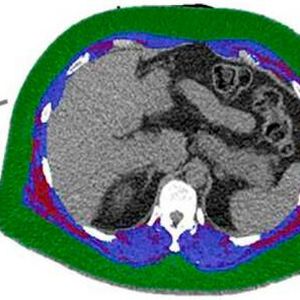

Researchers used CT scans to analyse each patient’s body composition, measuring the amounts and location of fat and muscle in a section of their torso.

All the patients were tested with cardiac positron emission tomography/computed tomography (PET/CT) scanning to assess how well their hearts were functioning. Researchers also used CT scans to analyse each patient’s body composition, measuring the amounts and location of fat and muscle in a section of their torso.

To quantify the amount of fat stored within muscles, researchers calculated the ratio of intermuscular fat to total muscle plus fat, a measurement they called the fatty muscle fraction.